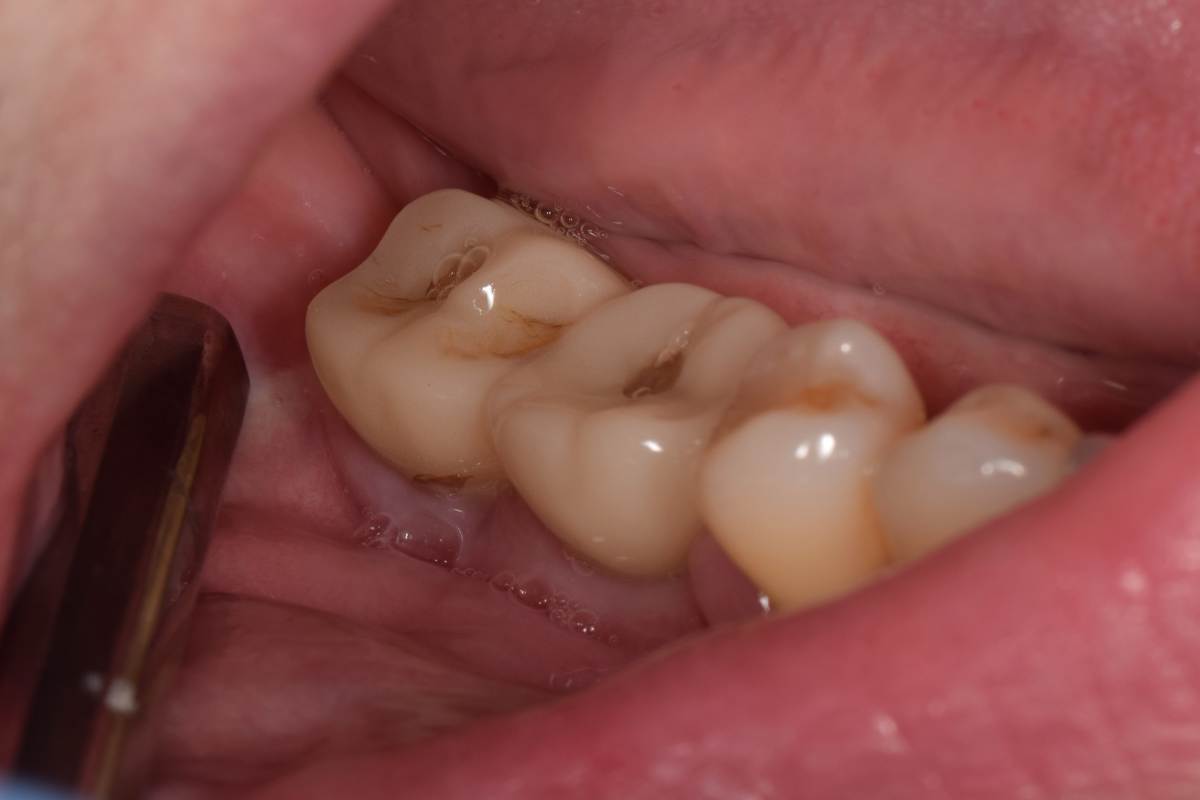

Нашел фото результата на времянках. Оно конечно не очень информативное,  был один и поэтому так получилось сфоткать

IMG_20250430_214632.jpg